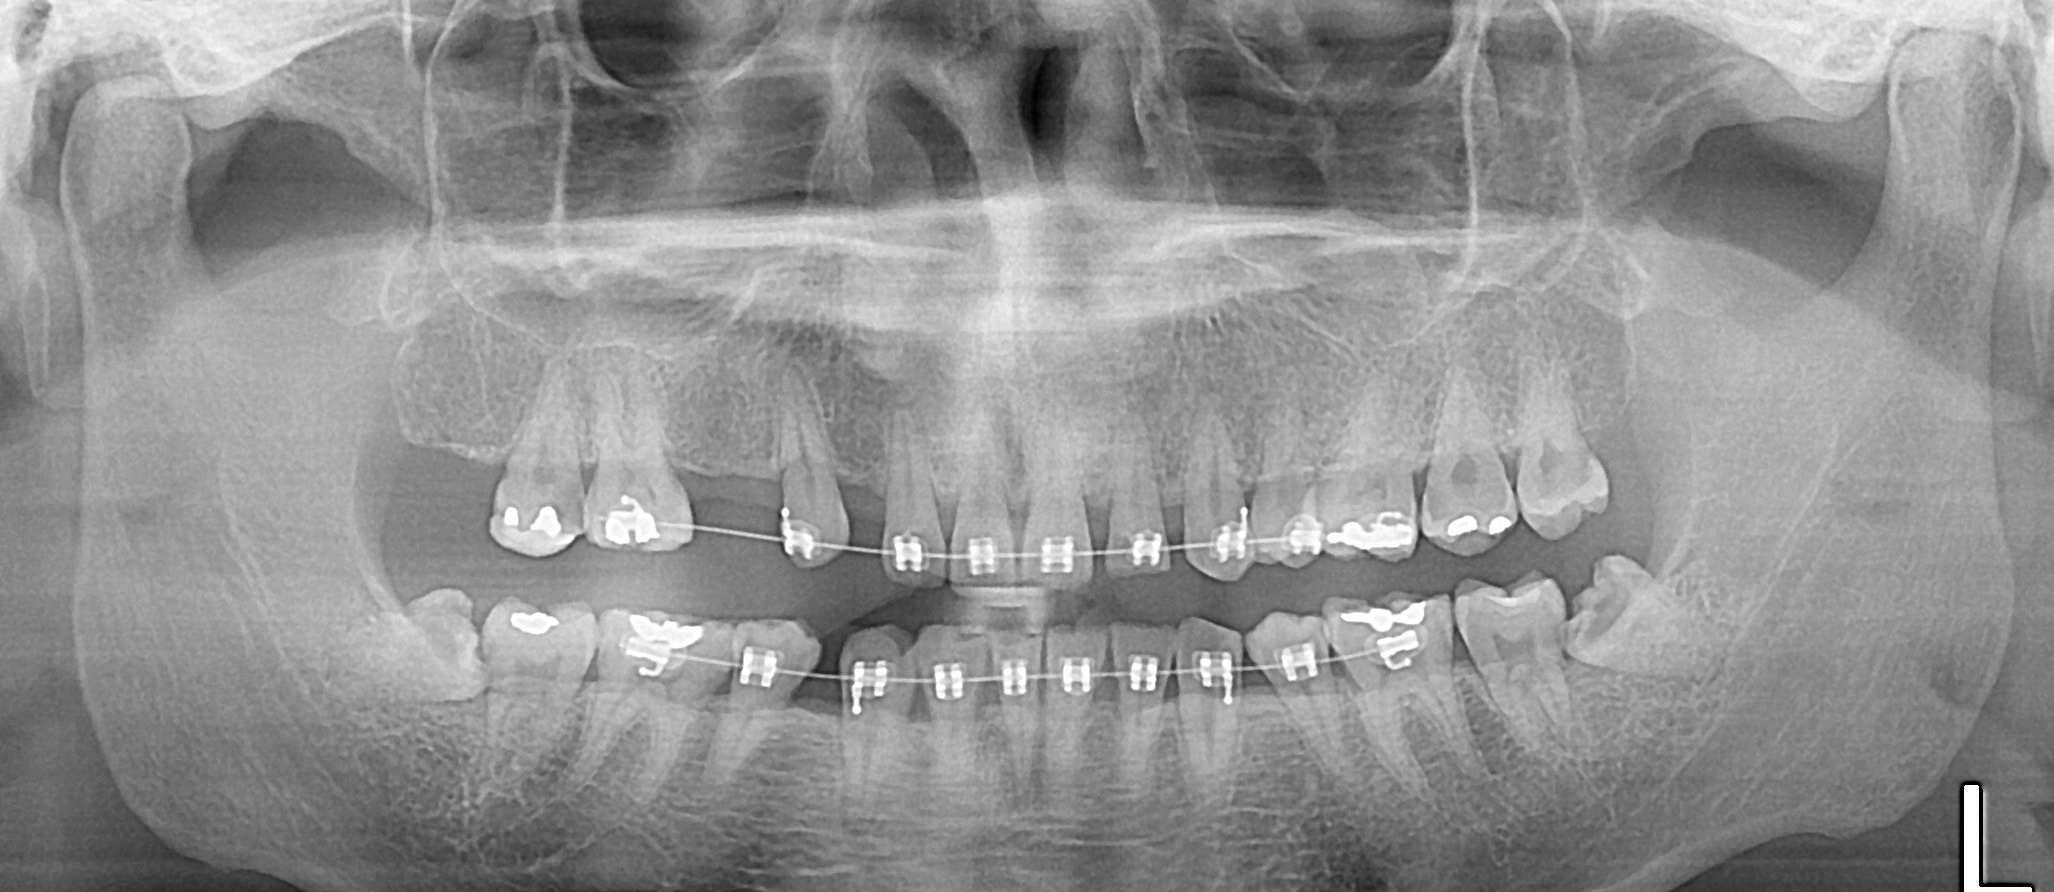

อยากสอบถามหน่อยครับว่ากรณีของผมฟันคุดผ่ายากไหม มีฟิล์ม ให้ดูครับ

1.อยากทราบว่าจากฟิล์มฟันผมด้านซ้ายทั้งบนและล่างคิดว่ายากไหมครับ

ตอนนี้ปวดฟันมาก ทานยามาหลายวันแล้ว

2.แล้วอยากรู้ว่าแนวเส้นประสาทคือตรงไหนหรือครับ

3.ผ่าฟันคุดน่ากลัวไม่ ผมกลัวหมอฟันมาก

4.ระหว่างผ่าฟันคุดกับปวดฟันอันไหนทรมานกว่ากัน